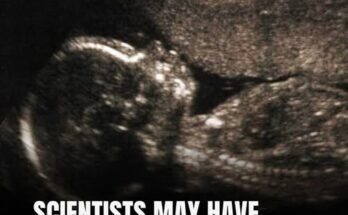

Test your eye skills: Where is the baby boy?

Here’s a challenge that will test not only your attention to detail but your sharpness of vision! Take a good look at this photo—it might seem simple at first, but …